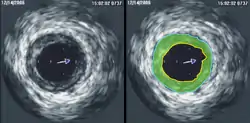

فیزیک پرتوشناسی تشخیصی:[پانویس 3] در این شاخه از فیزیک پزشکی، با مدالیتههایی همچون سی تی اسکن، ام آر آی (تصویر برداری تشدید مغناطیسی)، سونوگرافی، ماموگرافی، فلوروسکوپی، و رادیوگرافی معمولی میتوان سر و کار داشت.[17] فیزیک پرتوشناسی زیرمجموعهٔ این شاخه از فیزیک پزشکی است. طراحی و ضمانت کارکرد صحیح[پانویس 4] و کنترل کیفیت اینگونه دستگاهها بر عهدهٔ متخصصان فیزیک پزشکی میباشد.[18]

فیزیک پزشکی هستهای:[پانویس 13] با مدالیتههایی نظیر اسپکت، پت اسکن، سامانههای ترکیبی همانند پت-سیتی و اسپکت-سیتی و نیز روشهای تصویرسازی مولکولی سر و کار دارد؛ در واقع، این شاخه هم، زیرمجموعهای از پرتوشناسی تشخیصی است؛ اما از آنجا که مکانیزم تولید پرتو در این شیوه، بر خلاف منشأ فتوالکتریکی و عبوری، منشأ نشر یا گسیلِ از داخل[پانویس 14] دارد، این شاخه را بیشتر، جدای از سایر مدالیتههای متعارف در پرتوشناسی دانستهاند.[25]